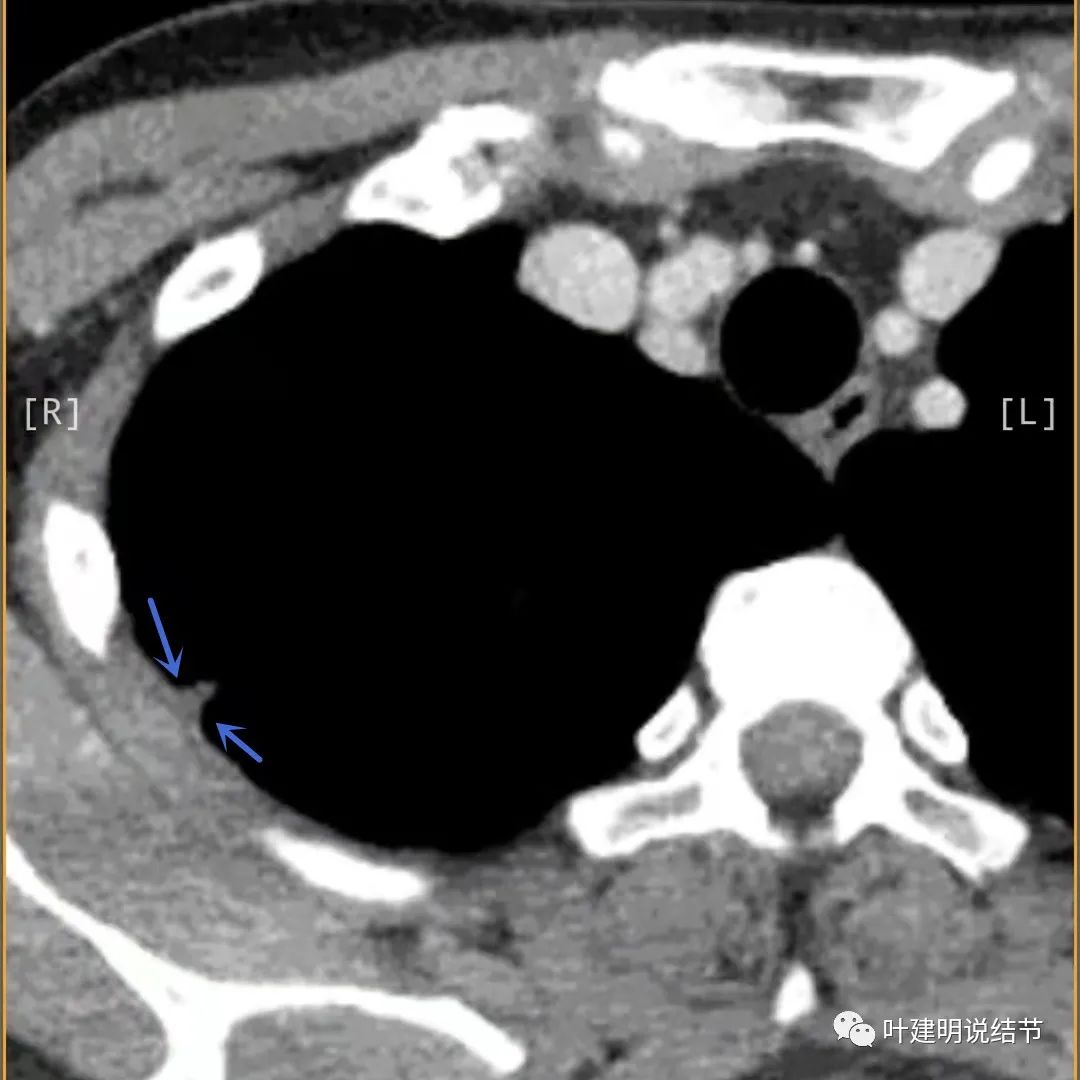

上面是她提供的病史资料,其中最重要的是PPD强阳性!其他主要看影像,我们先来看她2020年7月份的平扫片子(由于片子较多,详细展示是为了同道分析,我在影像特征描述上将只选取部分加以说明):

病灶邻近胸膜异常增厚(蓝色箭头)